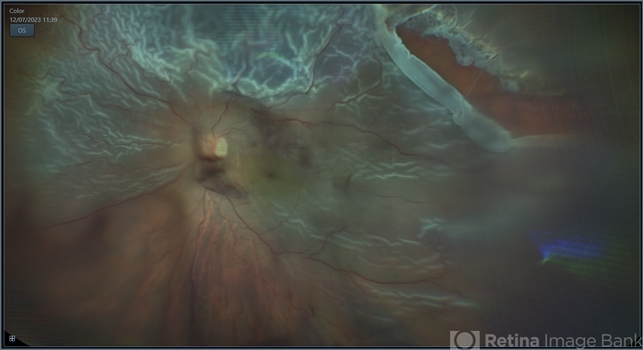

- rrd, chronic retinal detachment, peripheral lattice degeneration

- 78-year-old man with history of defective following cataract surgery showed total retinal detachment on examination